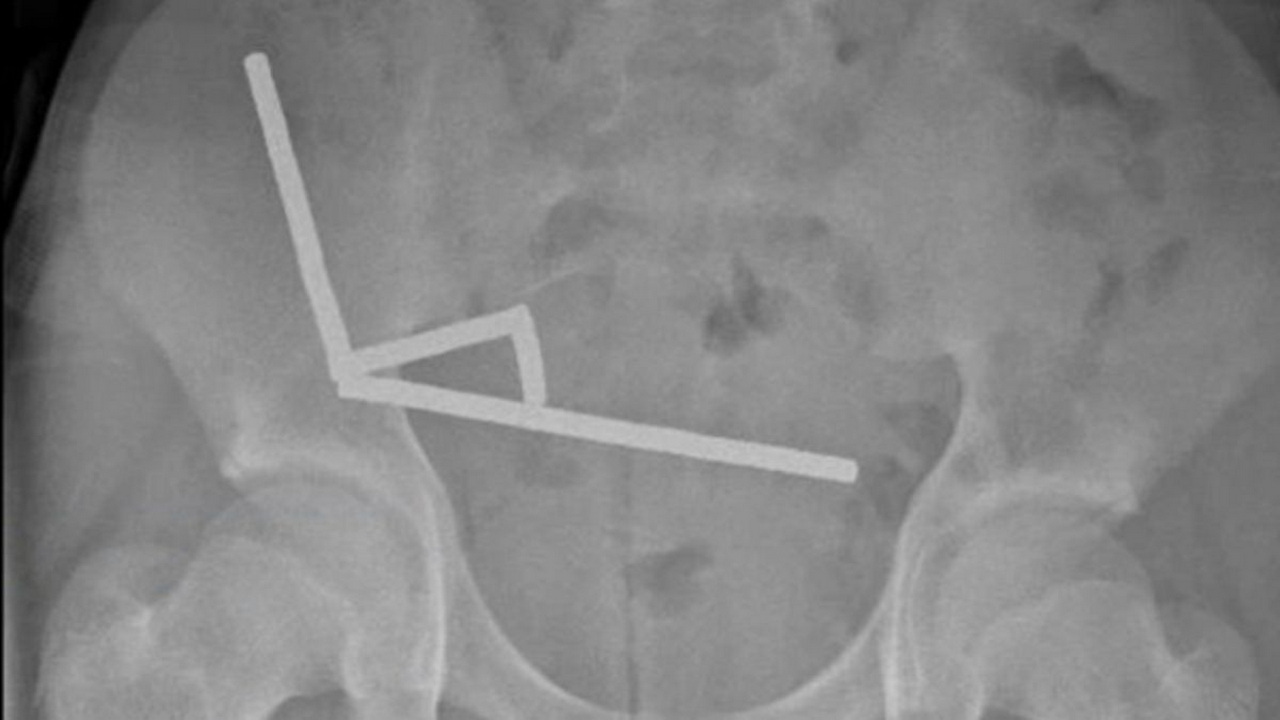

Μέσα στο έντερο, οι μαγνήτες ενώθηκαν σε τέσσερις ξεχωριστές αλυσίδες σε διαφορετικά σημεία του εντέρου και προκαλούσαν πίεση, η οποία οδηγούσε σε νέκρωση ιστού λόγω έλλειψης αιμάτωσης. Παρά τη σοβαρότητα της κατάστασης, ο έφηβος ανάρρωσε καλά και πήρε εξιτήριο μετά από οκτώ ημέρες. Το περιστατικό αυτό αναδεικνύει τον σοβαρό κίνδυνο που συνιστά η κατάποση μικρών, ισχυρών μαγνητών, οι οποίοι συχνά διατίθενται στην αγορά ως παιχνίδια για παιδιά και ενήλικες. Οι μαγνήτες αυτοί είναι πολύ ελκυστικοί στα παιδιά λόγω του μικρού μεγέθους τους και των φωτεινών χρωμάτων τους, γεγονός που αυξάνει τον κίνδυνο κατάποσής τους.

Εάν υπάρχει υποψία ότι ένα παιδί έχει καταπιεί μαγνήτη, είναι ζωτικής σημασίας να μεταφερθεί άμεσα σε νοσοκομείο, καθώς το 75% περίπου των περιστατικών απαιτεί χειρουργική επέμβαση ή ενδοσκόπηση για την απομάκρυνση των μαγνητών. Η πρόσβαση σε αυτούς τους ισχυρούς μαγνήτες αποτελεί αυξανόμενο πρόβλημα για την παιδιατρική υγεία, με τους γιατρούς και τους αρμόδιους φορείς να επισημαίνουν την ανάγκη για επαγρύπνηση και πρόληψη αυτών των επικίνδυνων καταστάσεων.